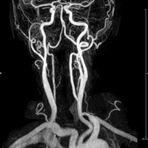

Halsgefäße

• intrakranielle Gefäße (Abklärung Verschluss, Stenose, Aneurysma)

• Halsgefäße zur Therapieplanung (z.B. Stent, Operation)

MR-Angiografie (MRA)

Angiographie ohne Kontrastmittel

• MR-Angiografie ohne Kontrastmittel

• Time of Flight (TOF)-Angiographie

• Phasenkontrastangiographie (PCA). Geeignet zur Quantifizierung Stenose-/Insuffizienzgrad z.B. bei Herzklappen, falls echokardiographisch die Untersuchungsbedingungen eingeschränkt sind.

Je nach Fragestellung und Körperregion Gefäßdarstellung ohne Kontrastmittel bei Kontrastmittelunverträglichkeit oder terminaler Niereninsuffizienz möglich.

Ganzkörper Angiographie mit Kontrastmittel

• MR-Angiographie mit Kontrastmittel

• Erfassung arterieller und venöser Gefäße/Bypässe aller Körperregionen mit 3D-Rekonstruktion

• je nach klinischer Fragestellung zeitaufgelöste MR-Angiographie (4D-MRA) z.B. bei Frage arteriovenöse Fistel/ Shunt oder Darstellung Unterschenkelarterien vor geplanter Bypassoperation.